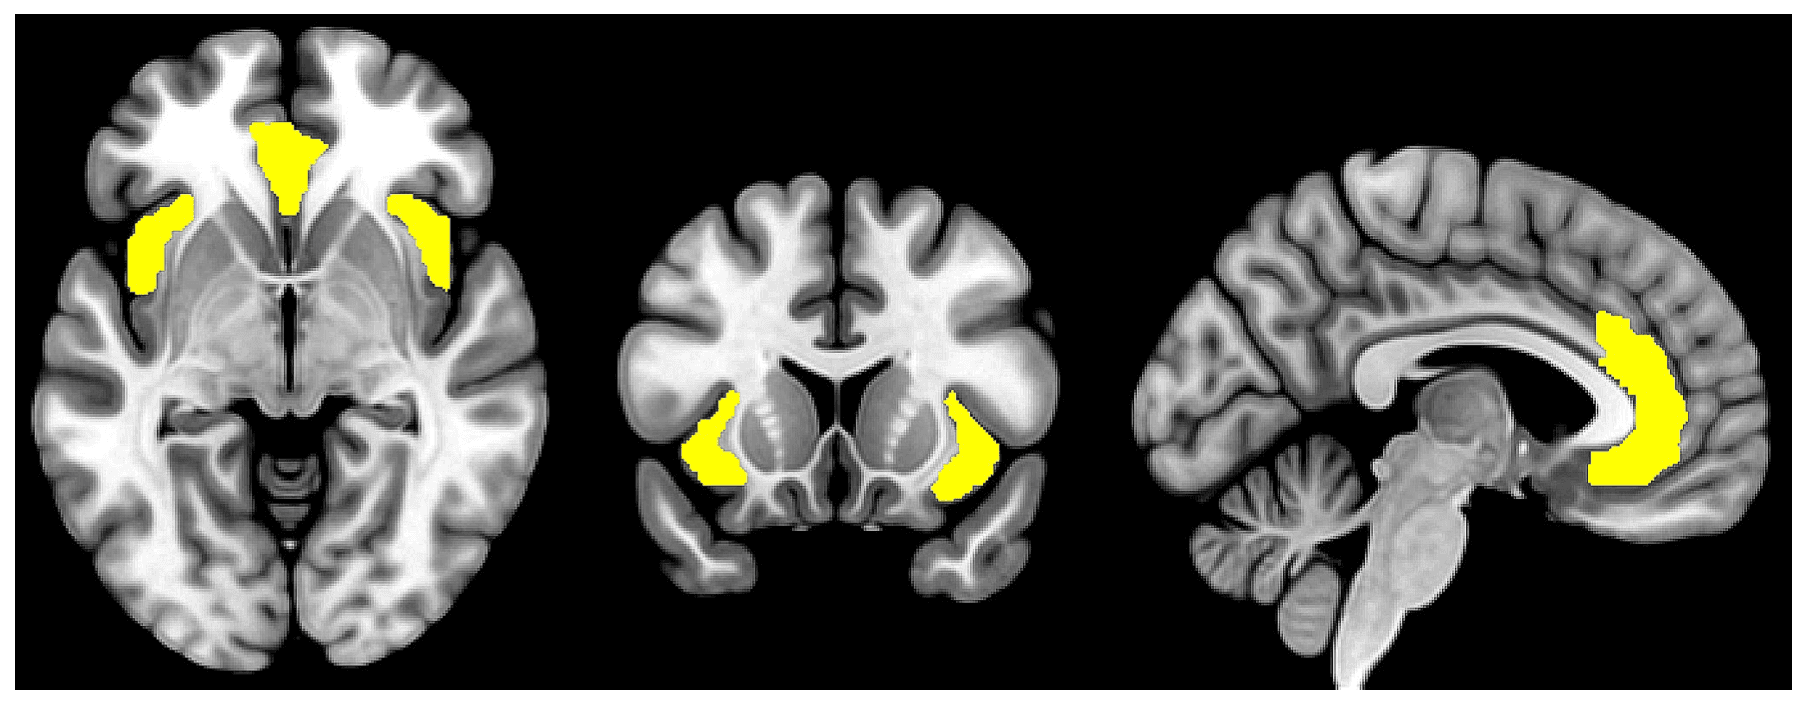

Studies of interregional brain connectivity using functional MRI have unveiled distinct large-scale networks of brain regions that support various cognitive processes. The SN is one of the most well-characterized brain networks and is involved in dynamically monitoring internal and external stimuli, directing attention toward salient and relevant information while filtering out distractions. It is primarily anchored in two hub regions: the bilateral AI and the dorsal portion of the ACC (see Fig. 1). Other brain regions, such as the ventrolateral prefrontal cortex, the inferior parietal lobule/temporoparietal junction, the thalamus, and the amygdala have also been considered components of the SN though with less clear consensus. While the exact anatomical boundaries of the SN are not well-defined, the reciprocal anatomical connections among the SN regions are assumed to underpin their coordinated neurocognitive functions that extend beyond mere sensory processing but also include affective processing, decision making, error monitoring, social cognition, interoceptive awareness, among others. Stimuli of high perceived importance and relevance consistently activate brain regions in the SN, which guides the direction of attention and cognitive resources toward the process of decision-making and behavior selection. The SN closely interacts with other brain networks such as the default mode network (DMN), which is involved in internally directed tasks (e.g. self-reflection) and mind-wandering, and the central executive network, which is involved in working memory and goal-directed cognitive processes. The seminal paper by Sridharan et al., later replicated by Goulden et al. using a different methodology, evidenced the role of the SN in cognitive flexibility, facilitating the switch between DMN and CEN in response to internally and externally salient stimuli, respectively. The SN is also functionally connected to various subcortical and limbic structures such as the amygdala, thalamus, and striatum, which collectively contribute to the encoding of stimuli that are of high emotional, hedonic, and homeostatic salience.